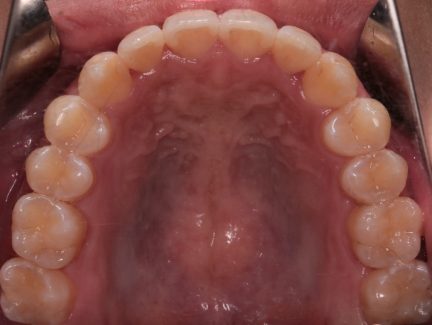

Case study 1

After